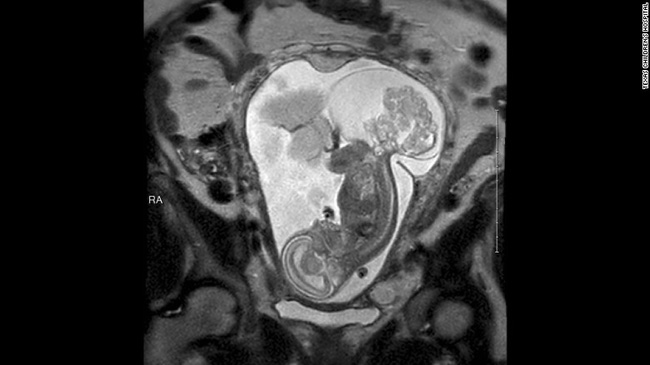

Kểt quả siêu âm ở tuần thứ 16 cho thấy, LynLee có một u quái vùng xương chậu.

Khi thai nhi được 23 tuần 5 ngày, tiến sĩ Darrell đã cùng với tiến sĩ Oluyinka Olutoye và ê kíp mổ đã tiến hành phẫu thuật khẩn cấp cứu LynLee. Tại thời điểm đó, khối u đã to gần bằng bào thai. Và ca phẫu thuật đã diễn ra trong vòng 5 giờ đồng hồ.